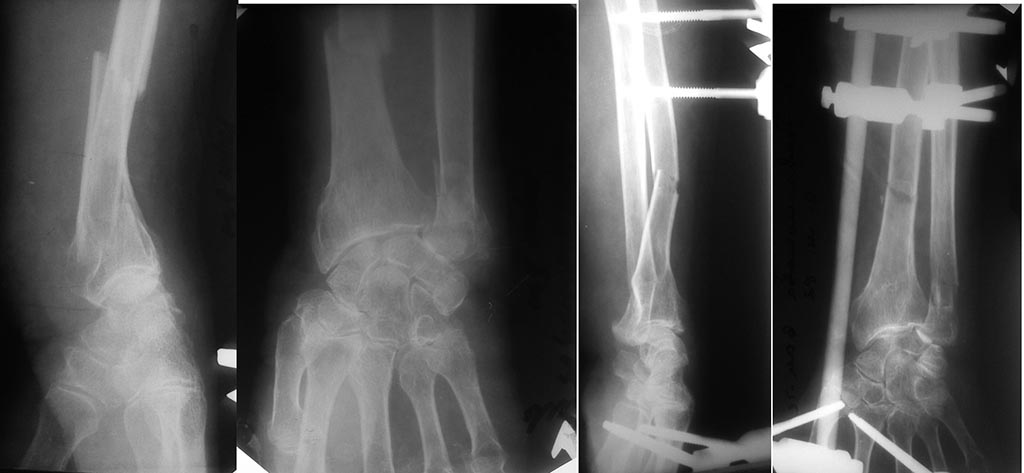

Уважаемые коллеги. Пациентка 82 лет, "сохранного вида" получила

вторичнооткрытый перелом костей левого предплечья. Рана по передней

поверхности, в области головки локтевой кости.

Около 20-ти лет назад был перелом лучевой кости в типичном месте,

который сросся с тыльным смещением.В ургентном порядке наложен АВФ. Рана

заживает первичным натяжением. Визуально предплечье ровное. Можно ли

оставить так как есть?